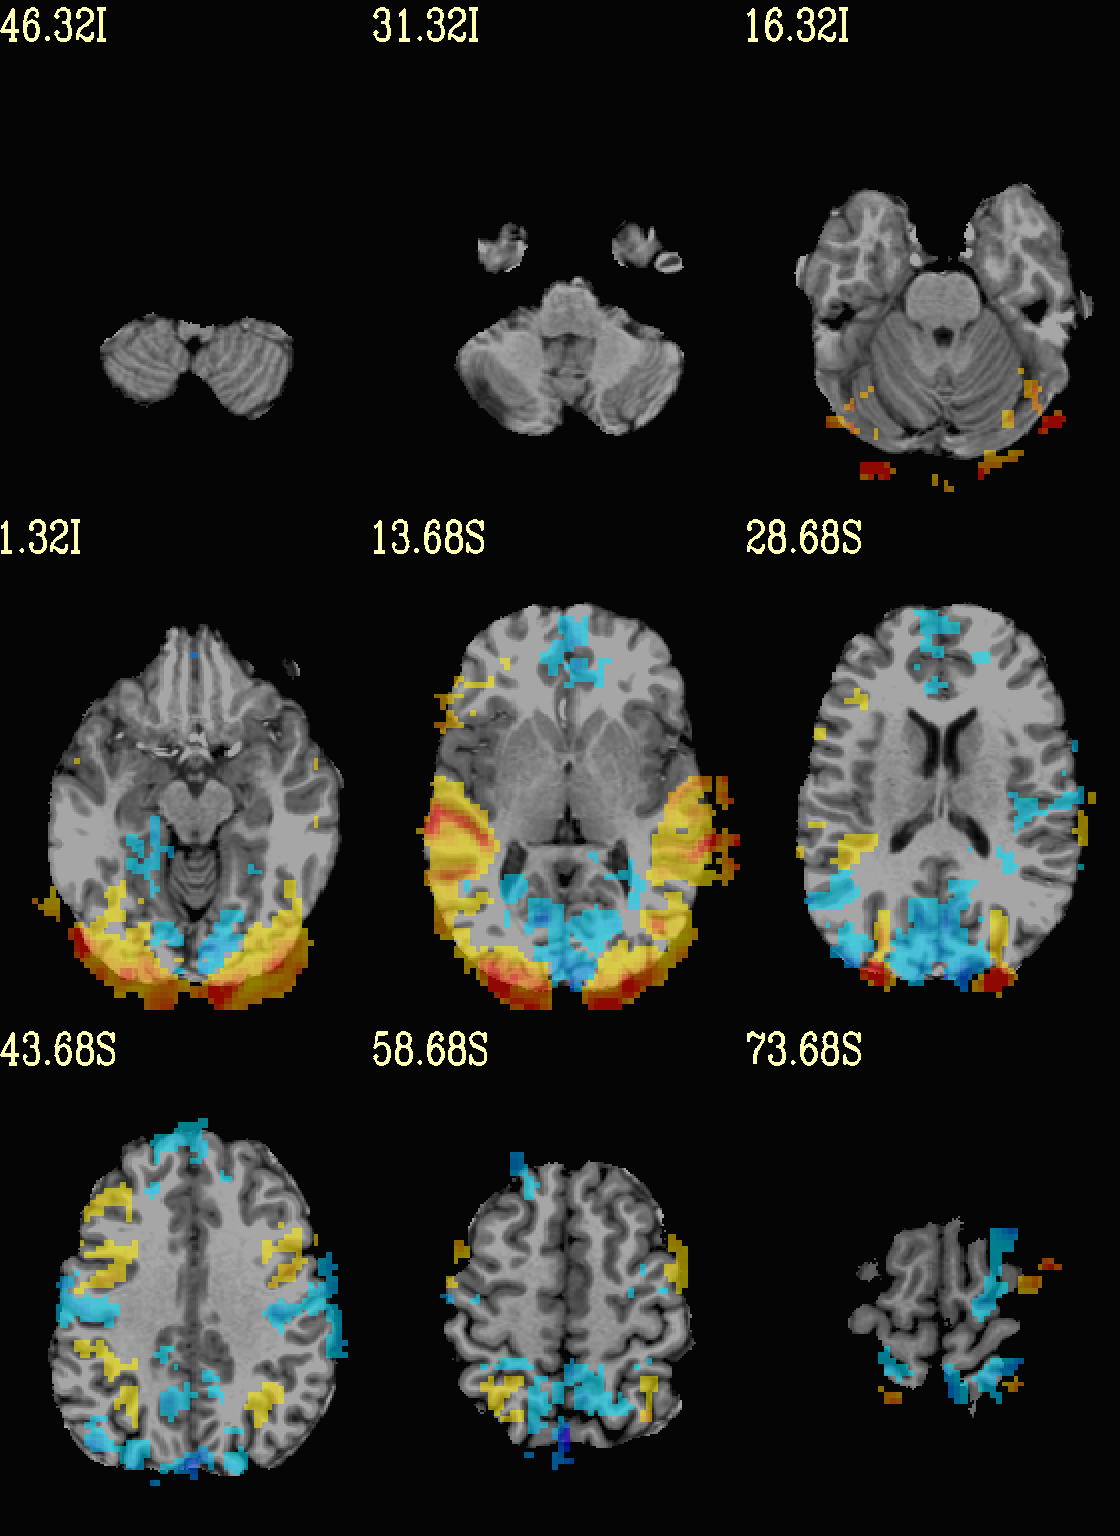

Ex. 7: Overlay beta coefs, threshold+clusterize translucently¶

Following on from the previous couple of examples, we can actually apply thresholding (by statistics) and clusterizing with translucent thresholding, using the alpha+boxed methodology from above. This can be a very useful way to highlight some results, while showing more results of modeling.

Therefore:

voxels that are both above voxelwise threshold and in a suprathreshold cluster will be opaque (or at max opacity) and boxed;

voxels that are above voxelwise threshold but not in a large enough cluster will be just slightly translucent and not boxed;

voxels that are below voxelwise threshold (and couldn’t even be in a cluster) will have the usual transparency increasing with their decreasing values.

As noted just above, one typically uses a mask when clusterizing (because the cluster size threshold would likely have come from looking at the spatial smoothness of noise just within the brain, not within the entire FOV). That mask can also be included in the commands clusterizing; conveniently, the final images will still show data from the entire FOV, and the boxed voxels will only be within the mask.

The only change from the previous command here is including a -mask

.. option in the chauffeur’s -clusterize .. option, as follows.

Note how the larger clusters that stuck outside the brainmask above

now show the mask’s boundary line—this is particularly apparent in

the posterior part of the brain/FOV.

set opref = QC/ca007b_Vrel_mskd

@chauffeur_afni \

-ulay strip+orig.HEAD \

-box_focus_slices AMASK_FOCUS_ULAY \

-olay func_slim+orig.HEAD \

-cbar Reds_and_Blues_Inv \

-ulay_range 0% 130% \

-func_range 3 \

-set_subbricks -1 "Vrel#0_Coef" "Vrel#0_Tstat" \

-clusterize "-NN 1 -clust_nvox 200 -mask mask.auto.nii.gz" \

-thr_olay_p2stat 0.001 \

-thr_olay_pside bisided \

-olay_alpha Yes \

-olay_boxed Yes \

-opacity 5 \

-prefix ${opref} \

-set_xhairs OFF \

-montx 3 -monty 3 \

-label_mode 1 -label_size 4

Example 7b |